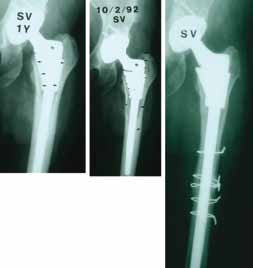

Painful S-Rom stem required on-lay strut grafting |

Stem Revisions

- 4 total (0 for aseptic loosening, 4 late sepsis)

Painful Hip

- 5 pts: Required on-lay grafting for signifi cant progressive end of stem pain.

Painful S-Rom stem required on-lay strut grafting